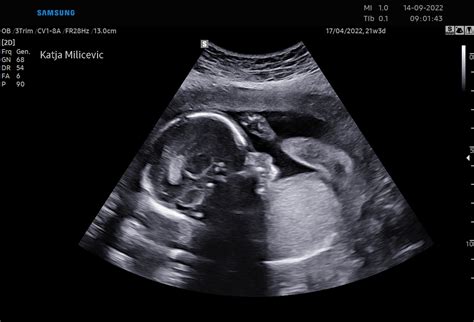

Ultrazvok in Prihajajoči Pregledi

Kmalu vas čaka še en zelo pomemben pregled - morfologija ploda. To je podroben ultrazvočni pregled, kjer zdravnik preveri celotno otrokovo telo, vključno z delovanjem možganov, srca, hrbtenice in drugih vitalnih organov. Ta pregled je ključen za zagotovitev, da se vaš otrok pravilno razvija in da ni prisotnih kakršnih koli nepravilnosti.

Morfološki ultrazvok